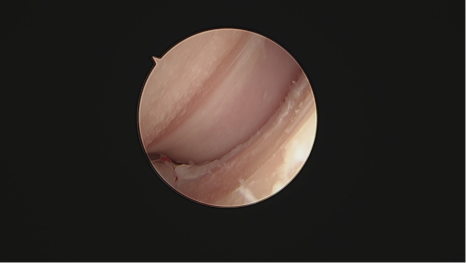

수술은 관절경을 이용하여 진행되었습니다.

팔꿈치 부위에 약 2~3mm 크기의 작은 구멍 생성

초소형 카메라를 통해 관절 내부 실시간 확인

통증을 유발하는 뼛조각 찾아낸 후 제거

손상된 연골 및 염증 조직 정리

대형견 강아지 관절경 수술 사진/ 출처: 에스동물메디컬센터

강아지 FMCP 관절경 진단 출처; 에스동물메디컬센터접기/펴기

관절경 수술은 주변 조직 손상을 최소화하기 때문에 수술 후 통증이 훨씬 적고, 회복 속도가 빠르다는 장점이 있습니다.